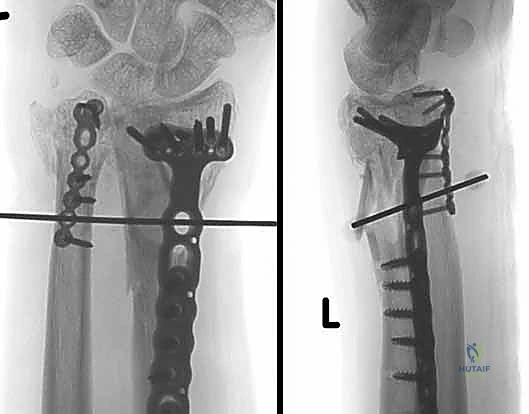

4. متلازمة انحشار الزند (Ulnar Impingement Syndrome) بعد الجراحات السابقة

هذا هو أحد أكثر الأسباب شيوعًا للجوء إلى استبدال رأس الزند الصناعي. تاريخيًا، كانت الجراحات القديمة مثل إجراء داراش (Darrach procedure) أو إجراء سوفي-كاباندجي (Sauvé-Kapandji) تعتمد على قص واستئصال جزء من عظم الزند لتخفيف الألم.

بينما كانت هذه العمليات تنجح مؤقتًا، إلا أنها على المدى الطويل تؤدي إلى مشكلة كبرى: عدم استقرار جذع الزند المتبقي. يبدأ جذع الزند المقطوع في التأرجح والاصطدام بعظم الكعبرة أثناء الحركة، مما يحفر تجويفًا مؤلمًا في الكعبرة.

يؤدي هذا الانحشار إلى:

* ألم شديد ومستمر.

* ضعف كارثي في قوة القبضة (Grip Strength).

* صعوبة بالغة في حمل الأشياء.

* شعور بـ "طقطقة" أو "فرقعة" مؤلمة عند تدوير الساعد.

خطوات جراحة استبدال رأس الزند الصناعي بالتفصيل

تتطلب هذه الجراحة دقة متناهية وفهمًا عميقًا للتشريح الدقيق لليد والرسغ، وهو ما يميز الأستاذ الدكتور محمد هطيف كأستاذ جامعي وخبير في الجراحة المجهرية.

3. إزالة العظم التالف وتحضير القناة

يتم فتح كبسولة المفصل. إذا كان رأس الزند موجودًا ولكنه مشوه، يتم قصه باستخدام منشار جراحي دقيق. في الحالات التي تم فيها استئصال رأس الزند مسبقًا، يتم تنظيف جذع الزند المتبقي. بعد ذلك، يتم تحضير القناة النخاعية داخل عظم الزند باستخدام مباسط (Broaches) متدرجة الحجم لاستقبال جذع المفصل الصناعي.

4. اختيار وتجربة المفصل الصناعي (Sizing and Trialing)

هذه خطوة حاسمة. يقوم الدكتور هطيف بوضع نماذج تجريبية (Trials) للمفصل الصناعي بأحجام مختلفة. يتم اختبار حركة الساعد (الكب والاستلقاء) للتأكد من السلاسة، والاستقرار، وعدم وجود أي احتكاك، والتأكد من استعادة الطول الصحيح للزند.

5. زراعة المفصل النهائي

بعد تحديد الحجم المثالي، يتم إدخال المفصل الصناعي النهائي. تتكون معظم المفاصل الحديثة من جذع معدني (غالبًا من التيتانيوم) ورأس أملس (قد يكون معدنيًا أو من السيراميك أو البايروكربون). يتم تثبيت الجذع داخل العظم إما بالضغط (Press-fit) أو باستخدام الأسمنت العظمي، حسب جودة عظام المريض.

6. إعادة بناء الأنسجة الرخوة (الخطوة الأهم للاستقرار)

ما يميز الجراح الخبير هو كيفية تعامله مع الأنسجة الرخوة. يقوم الأستاذ الدكتور محمد هطيف بخياطة وإعادة ربط كبسولة المفصل ومجمع الغضروف الليفي الثلاثي (TFCC) حول المفصل الصناعي الجديد. يتم تمرير خيوط قوية عبر ثقوب مخصصة في المفصل الصناعي لضمان تثبيت الأربطة بشكل محكم، مما يمنع خلع المفصل مستقبلاً.